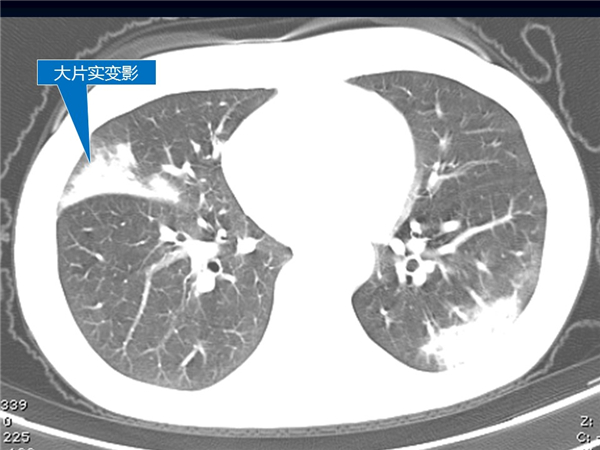

【病例分享】新型冠狀病毒感染肺部CT影像4例(常德市第一人民醫(yī)院)

幻燈片5.jpg